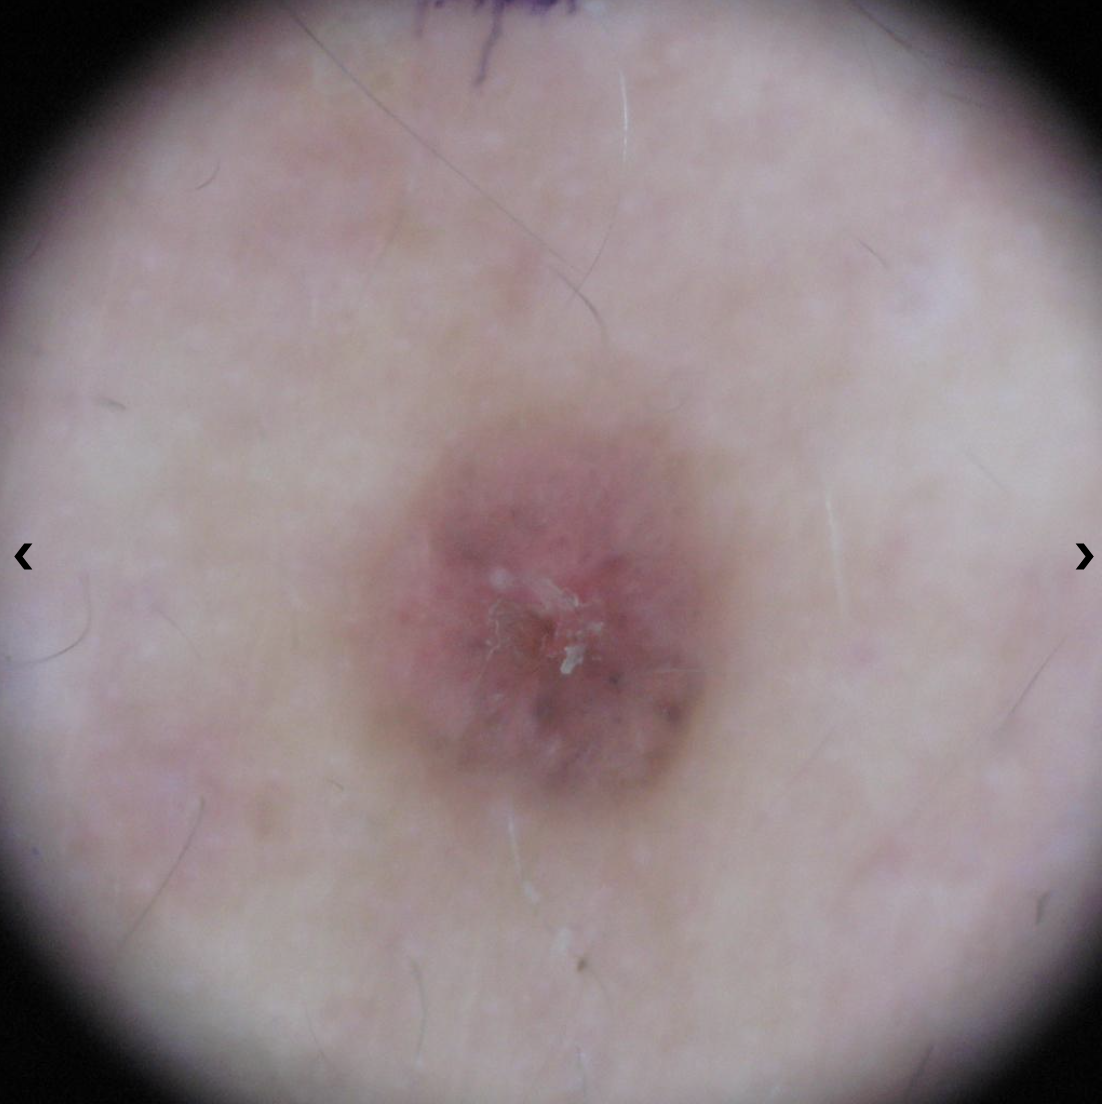

A small pink growth with a slightly raised, rolled edge and a crusted indentation in the center. (BCC)